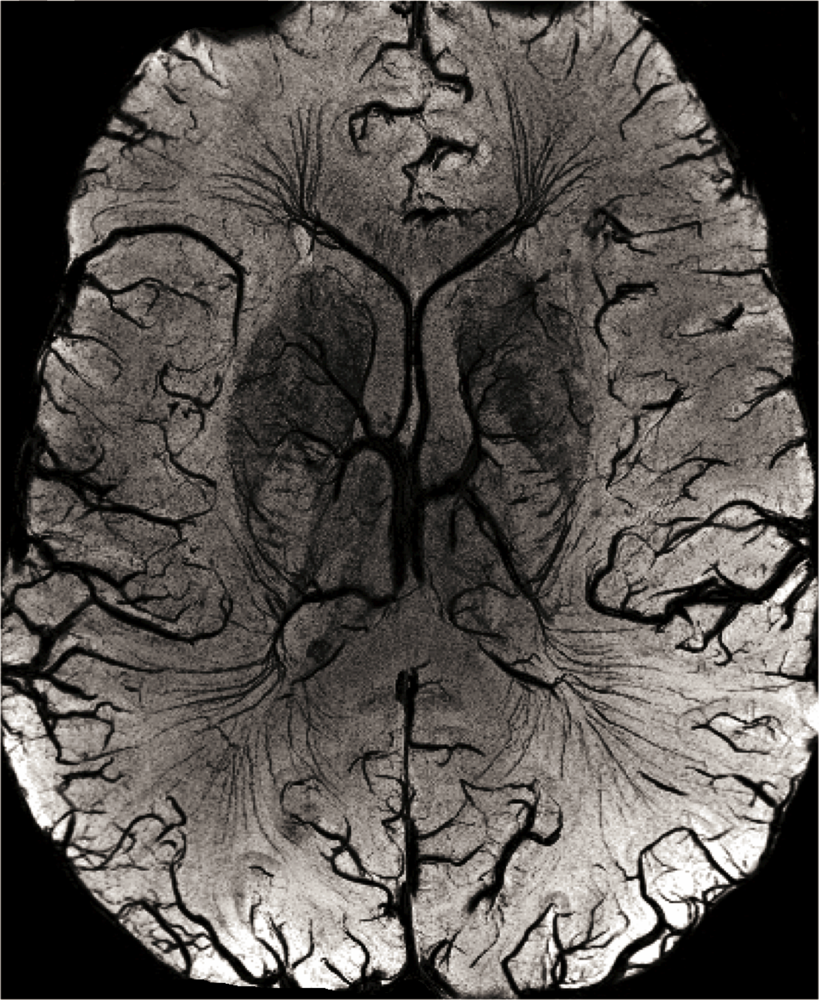

2.1. High-Resolution Structural MRI

- Reichenbach, J.R.; Barth, M.; Haacke, E.M.; Klarhofer, M.; Kaiser, W.A.; Moser, E. High-resolution MR venography at 3.0 Tesla. J. Comput. Assist. Tomogr 2000, 24, 949–957. [Google Scholar]

- Lee, B.C.; Vo, K.D.; Kido, D.K.; Mukherjee, P.; Reichenbach, J.; Lin, W.; Yoon, M.S.; Haacke, M. MR high-resolution blood oxygenation level-dependent venography of occult (low-flow) vascular lesions. AJNR Am. J. Neuroradiol 1999, 20, 1239–1242. [Google Scholar]

- Essig, M.; Reichenbach, J.R.; Schad, L.R.; Schoenberg, S.O.; Debus, J.; Kaiser, W.A. High-resolution MR venography of cerebral arteriovenous malformations. Magn. Reson. Imaging 1999, 17, 1417–1425. [Google Scholar]

- Tan, I.L.; van Schijndel, R.A.; Pouwels, P.J.; van Walderveen, M.A.; Reichenbach, J.R.; Manoliu, R.A.; Barkhof, F. MR venography of multiple sclerosis. AJNR Am. J. Neuroradiol 2000, 21, 1039–1042. [Google Scholar]

- Barth, M.; Nobauer-Huhmann, I.M.; Reichenbach, J.R.; Mlynarik, V.; Schoggl, A.; Matula, C.; Trattnig, S. High-resolution three-dimensional contrast-enhanced blood oxygenation level-dependent magnetic resonance venography of brain tumors at 3 Tesla: first clinical experience and comparison with 1.5 Tesla. Invest. Radiol 2003, 38, 409–414. [Google Scholar]

- Schad, L.R. Improved target volume characterization in stereotactic treatment planning of brain lesions by using high-resolution BOLD MR-venography. NMR Biomed 2001, 14, 478–483. [Google Scholar]